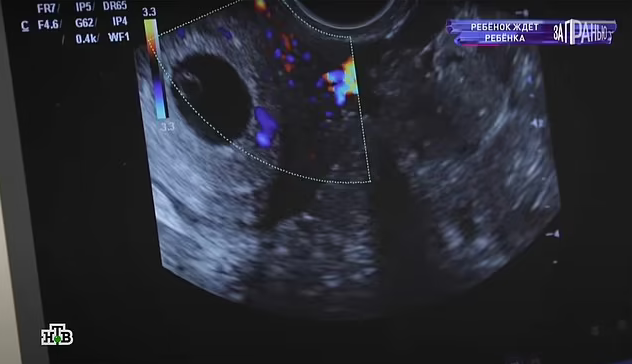

A 12-year-old schoolgirl has revealed that she is pregnant as cops interrogate her adult ex-boyfriend over the alleged rape.

The young girl and her lover broke up but she is “delighted” to be expecting. She is intending to raise her child with her mother, 42-year-old Elena, while continuing her education.